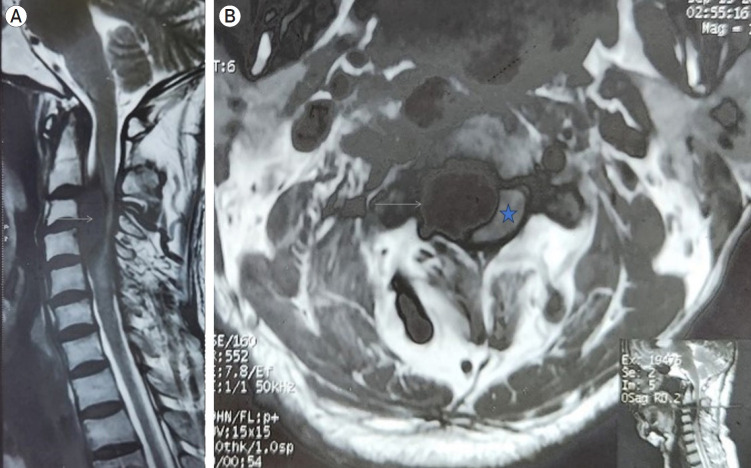

Vertebral-venous fistula (VVF) is a rare vascular disorder characterized by an atypical, direct, high-flow shunt between an extracranial vertebral artery and its adjoining vein. While it can originate spontaneously in association with conditions affecting the vascular wall, trauma is also a recognized etiological factor. We report a case of a 64-year-old gentleman with multiple neurofibromas who presented with a cervical VVF leading to cervical myelopathy, successfully managed with endovascular coiling. The condition's rarity and the complex vascular anatomy involved have hindered the development of standardized management guidelines. Our experience aligns with literature indicating that endovascular treatment can be a safe and effective approach for VVF.